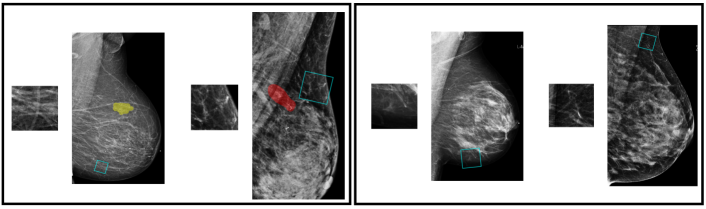

During training, we consider patches from mammograms with and without lesions, and perform multi-class classification over four classes: malignant, benign, outside and negative. In the validation and test phases, we only consider patches from images with lesions, and transform the patch-level predictions into a malignancy prediction for each lesion in the images. To get a prediction for a lesion, as shown in Figure 5, we crop 100 patches that overlap with the segmentation of the lesion. The size of the cropping window varies from 128128 to 384384 pixels, which is the same range we used for data augmentation. After cropping, each patch is resized to 256256 pixels, and we use it as input to to produce a feature vector. Then, we apply on the concatenated maps, including the embedding maps transformed by the feature vector and we get its prediction, each as four scores for the four patch classes. For each patch, we normalize the scores for malignant and benign patch classes so that they sum to one. Finally, we average the 100 normalized scores of the 100 sampled patches to obtain a prediction for the lesion. Based on these estimated probabilities, we compute the AUC that the model achieves in classifying the lesions as malignant or benign. We use the AUC computed on the 850 lesions from the validation set for model selection, and report the AUC computed for the 600 lesions from the test set.

![]() |